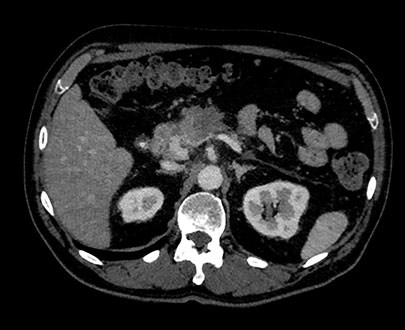

В режиме MonoE показаны синтезированные моноэнергетические изображения с предустановленными значениями кВп в диапазоне от 40 до 200 кВп. При изменении значения кВп также происходят изменения на изображении, даже при сохранении настроек окна/уровня. Например, при более низком значении кВп йод может проявляться ярче, а при более высоком значении количество артефактов от металлических объектов может быть снижено.